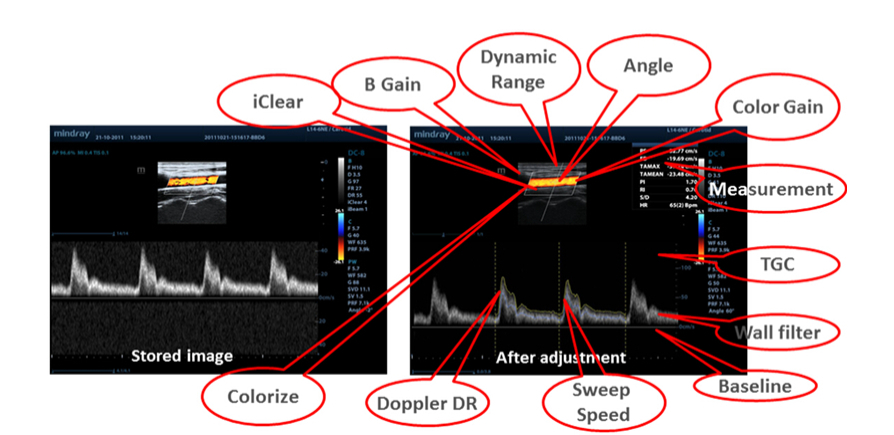

Datos en bruto

Permite una flexibilidad ├│ptima para el posprocesamiento de las im├Īgenes almacenadas, incluidos el ajuste de par├Īmetros, y la adici├│n de comentarios y mediciones, lo que permite una productividad m├Īxima durante el escaneo.